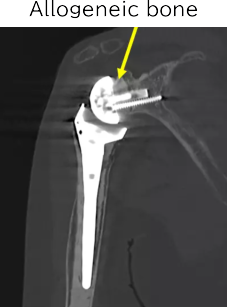

Therefore, a shaped allograft is attached to the baseplate to fit the deformed glenoid.

The baseplate with the allograft is fixed to the glenoid.

The glenosphere is attached.

Postoperative X-ray

CT scan six years after surgery